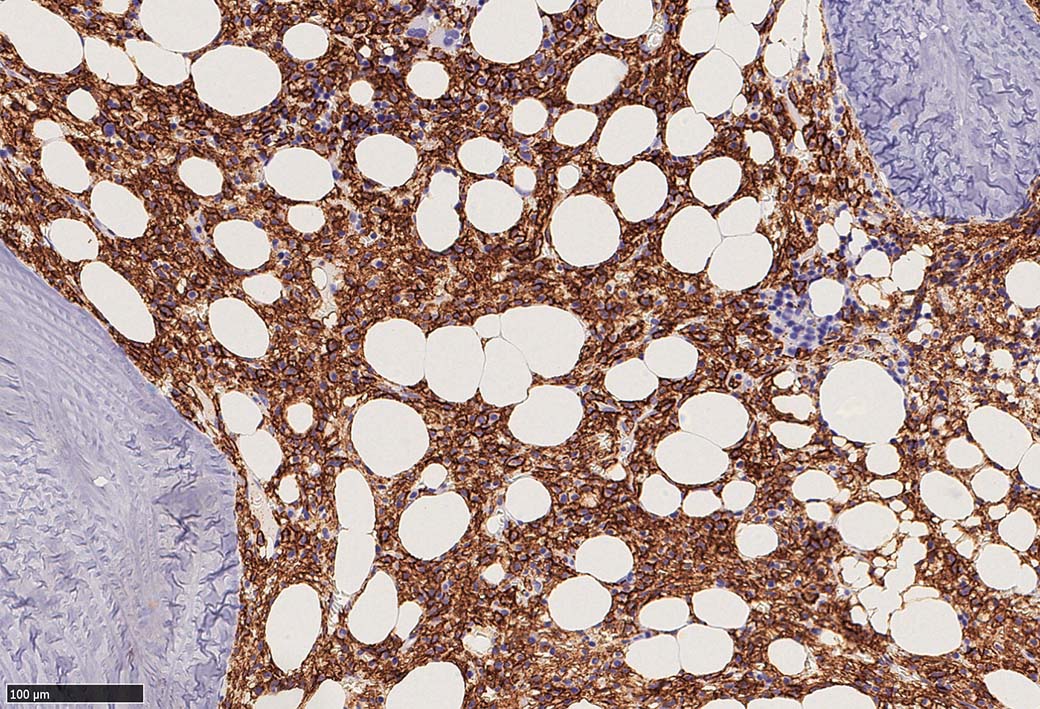

増殖細胞はCD20(相変わらずべったり染まる), CD19, PAX5陽性 CD25陽性.

BRAF V600E変異タンパクの免疫染色(山梨医大 大石先生に染色していただきました. ベンタナ, Optiview)